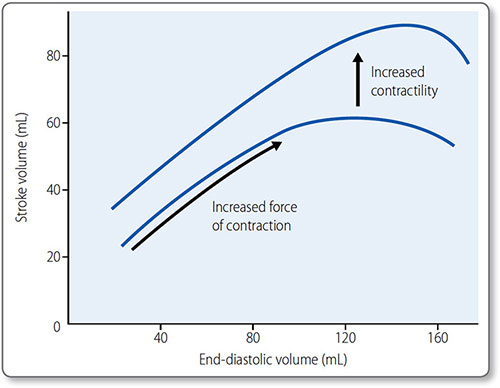

Cardiac preload Preload is end-diastolic ventricular pressure. An increase in preload increases end-diastolic and stroke volume.

The myocardium is at its most stretched at the end of diastole, which has two effects:

- More active actin–myosin cross-bridges form

- The affinity between Ca2+ and troponin C increases.

This is the basis for the Frank–Starling law: ‘the mechanical energy discharged during ventricular systole is a function of initial fiber length’, i.e. more myocardial stretch leads to a more forceful contraction (Figure 1.30). This is how:

- Left and right circulations equalize

- Exercise increases venous return and therefore CO

- Reduced venous return (e.g. hemorrhage) decreases CO.

Venous muscular tone can also affect venous return:

- An increase – e.g. sympathetic activation – increases venous return

- A decrease in tone decreases venous return.

Figure 1.30: The Frank−Starling curve. An increase in end-diastolic volume results in a greater stroke volume. In the physiological range, the curve is steep as ventricles are particularly sensitive to changes in end-diastolic volume. Beyond the physiological range, the curve plateaus; further increases in end-diastolic volume do not increase stroke volume. The effect of raised contractility (often referred to as increased sympathetic tone) is demonstrated in the upper curve.

Contractility Contractility is the force of myocardial contraction, independent of preload. Inotropes affect contractility (Table 1.12) and are also the name of a class of drugs with positive inotropic effects ((e.g. digoxin; see page 156).

A positive inotropic agent – such as sympathetic activation or increased myocardial stretch – increases cardiomyocyte contraction, usually by increasing Ca2+ influx, which causes more actin−myosin cross-bridges to form.

Sympathetic activation increases contractility and heart rate via β1 adrenoreceptors (see page 39). An increase in contractility shifts the Frank–Starling curve upwards.

Parasympathetic activation reduces rate but has no effect on contractility due to minimal parasympathetic innervation of myocardium.